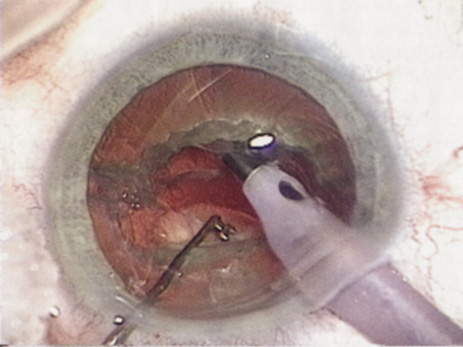

HYDRODISSECTION

Hydrodissection can be performed after the surgeon has successfully completed capsulorrhexis.97 If the capsulorrhexis is not intact, fluid forced around the interior of the capsule may cause the bag to splay open. With capsulorrhexis, hydrodissection is a safe and extremely useful maneuver. Hydrodissection can be thought of as two maneuvers: hydrodelineation and cortical cleaving hydrodissection. By placing a 27-gauge cannula on a syringe filled with balanced saline solution (BSS), the surgeon can direct fluid beneath the residual anterior capsular rim to create a cleavage plane. Depending on the direction the fluid wave takes, different lamellae of the cataract will be separated. Hydrodelineation is the term used when the cleavage plane separates the adult nucleus from the fetal nucleus or the adult nucleus from the more peripheral epinucleus. Hydrodelineation often results in the characteristic golden ring sign (Fig. 11). Cortical cleavage occurs when the cortex is separated from the capsular bag (Fig. 12). Finding the cortical cleavage plane may be facilitated by gently lifting the capsular margin away from the cortex with the BSS cannula before injecting. Several small bursts of fluid allow the surgeon to monitor progress of the fluid wave. When dealing with a soft nucleus, the authors strive to perform true cortical cleaving hydrodissection. For a hard nucleus, hydrodelineation allows manipulation of less of the nuclear bulk, although the remaining epinuclear shell must be addressed in an additional step. Hydrodelineation is particularly useful if the nucleus is not freely mobile after cortical cleaving hydrodissection.

Fig. 11. A crisp “golden ring” is seen from the fluid cleft between the epinucleus and nucleus with hydrodelineation.

Fig. 12. Hydrodissection, performed subincisionally with a 27-gauge J-cannula, produces a cleavage plane between the capsule and the cortex. The small blue arrows indicate the advancing fluid wave.